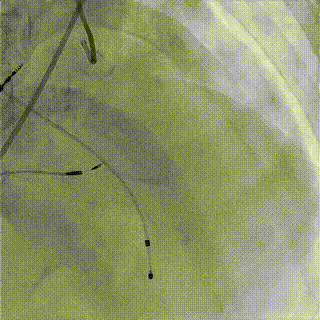

手术过程

1.LAD+LCX造影

2.右冠造影

3.主动脉根部造影

4.18mm球囊预扩

5.跨弓+跨瓣

6.释放至工作位

7.完全释放

8.术后造影,冠脉血流通畅

瓣膜释放后,复查左室-主动脉瓣峰值压差0-1mmHg,食道超声及造影像均提示瓣膜无反流,冠脉血流通畅。